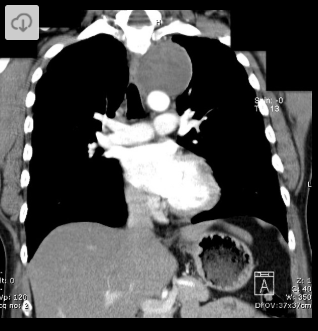

2 anos, masculino

Cisto de duplicação esofágico

Predleção por meninos; diagnosticados na infância

Em geral assintomáticos; podem provocar estridor

Mais comuns no esôfago distal; geralmente não comunicam com a luz do esôfago;

TC: Cisto com densidade de líquido, margens bem definidas que podem realçar com contraste; podem complicar com hemorragia, infecção: nível liquido, espessamento parietal.